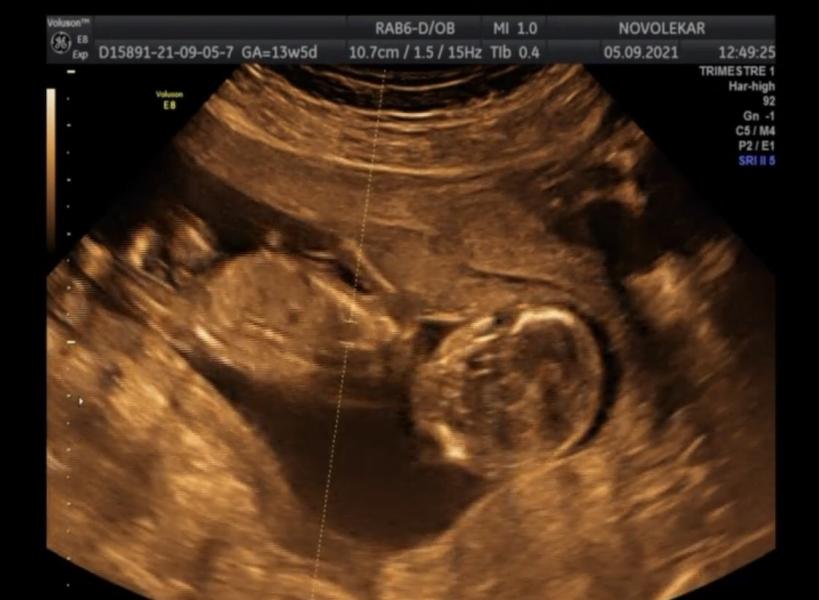

Вот так выглядит мальчик на 13 неделе 😀 думаю не перепутали )